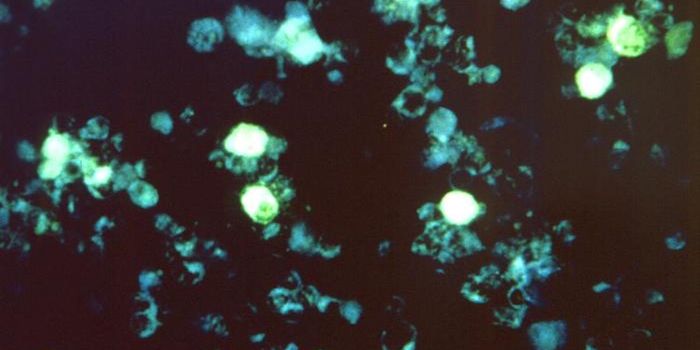

OCT 17, 2023Clinical & Molecular DXIn this photo, courtesy UC San Diego Health Sciences, regenerating neurons (yellow) can be seen along with non-regenerat ...